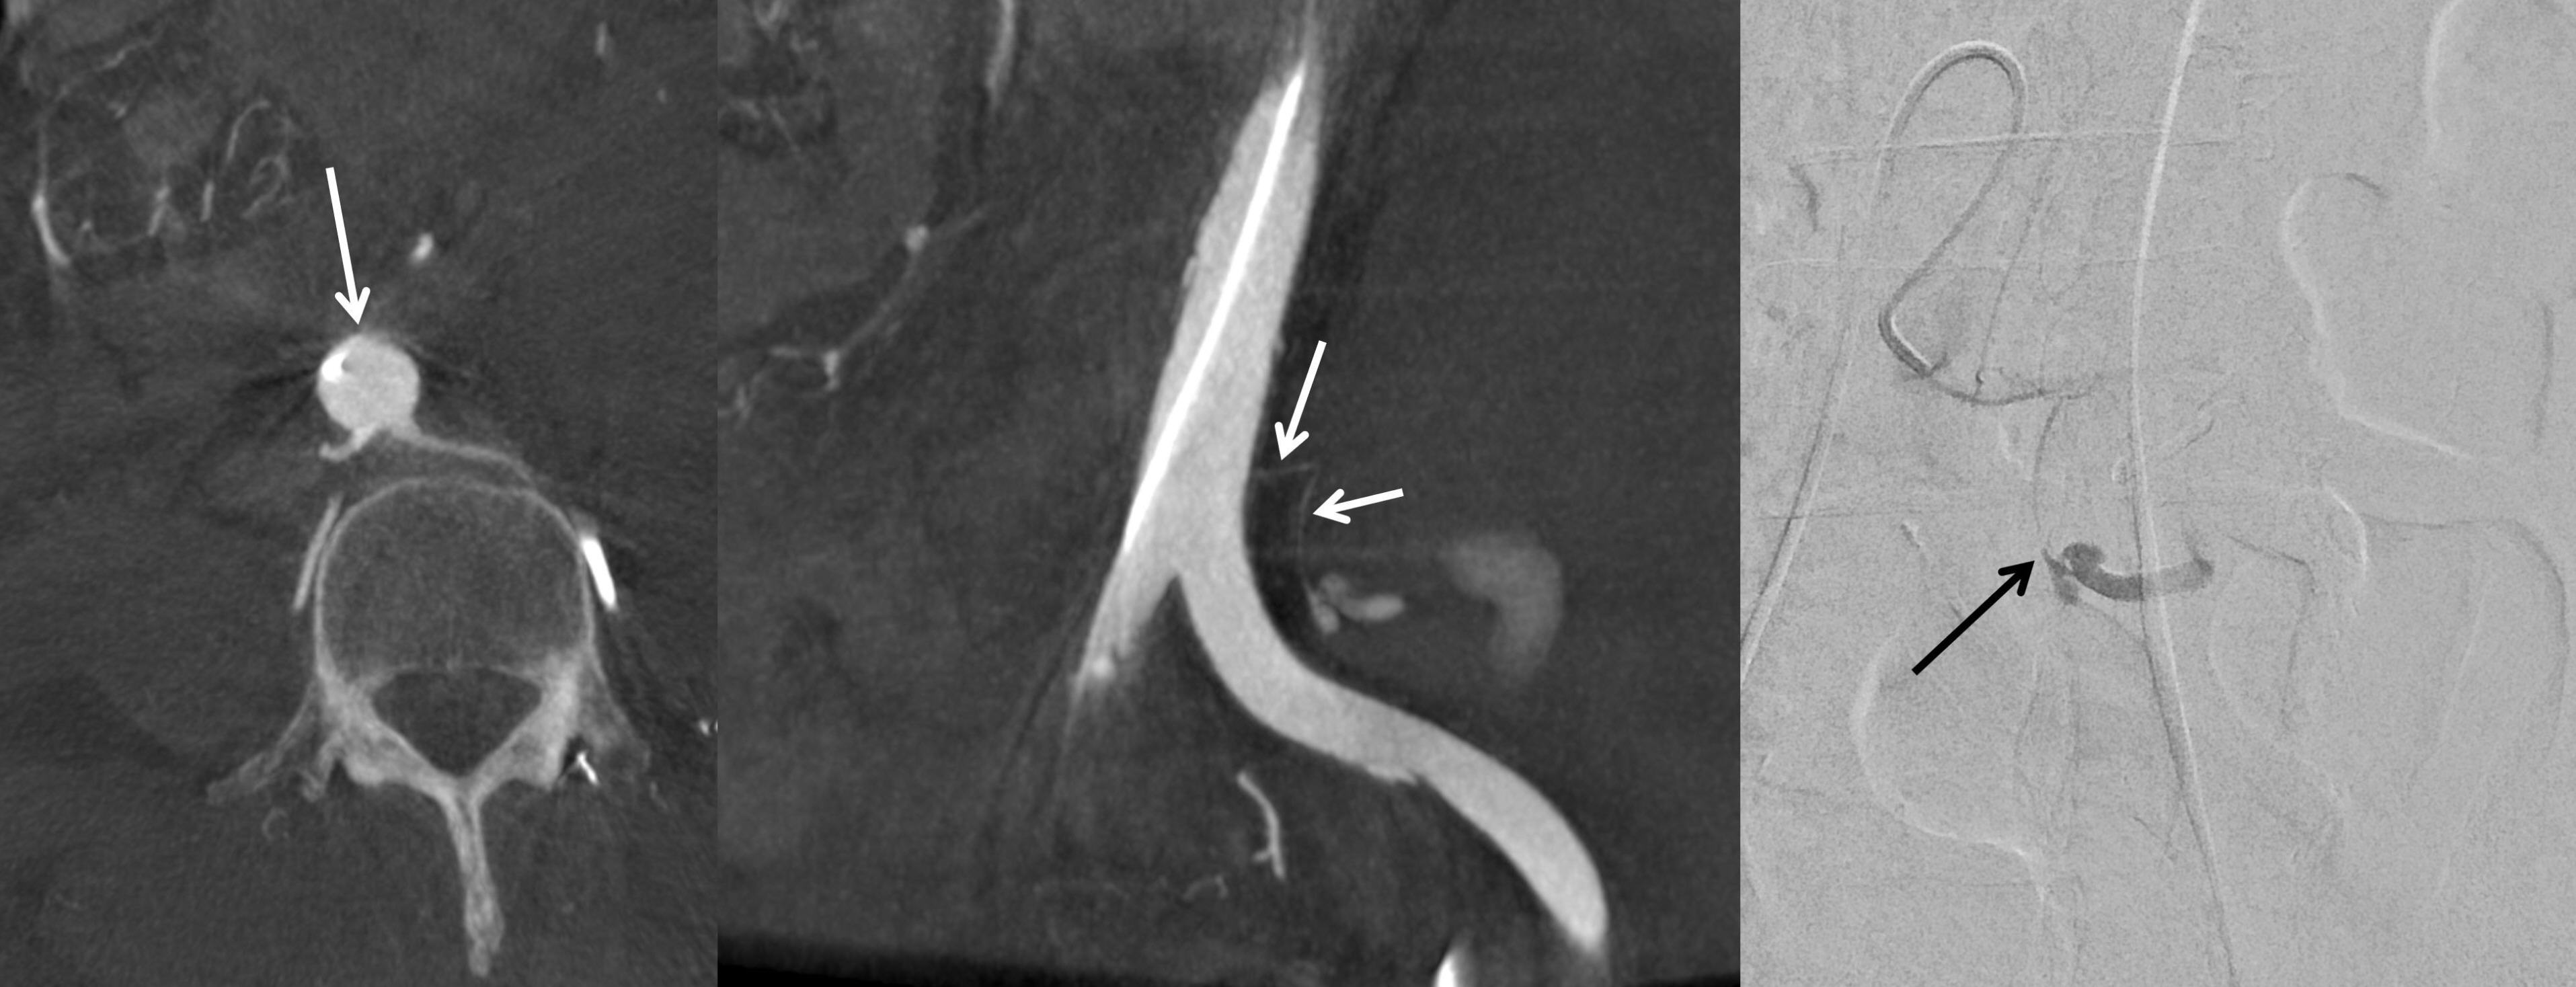

3, and an INR of 1.02. Contrast-enhanced thoracoabdominal CT, performed to identify possible bleeding sources, demonstrated a left retroperitoneal hematoma with active extravasation (

Fig. 1). Associated fractures were noted in the left iliac bone at the anterior superior iliac spine and the left transverse process of L5. There was no evidence of hematuria or hydronephrosis.

Fig. 1.Preprocedural contrast-enhanced abdominopelvic CT reveals a left retroperitoneal hematoma with associated contrast media extravasation (asterisk).